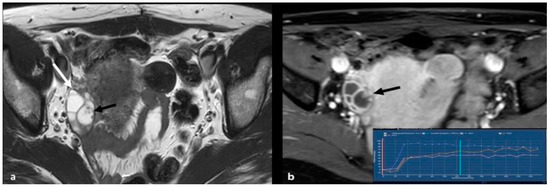

2.2.3. Pelvic Inflammatory Disease—Tubo-Ovarian Abscess (TOA)

2.3. Rare Ovarian Neoplasms That Can Mimic EOC